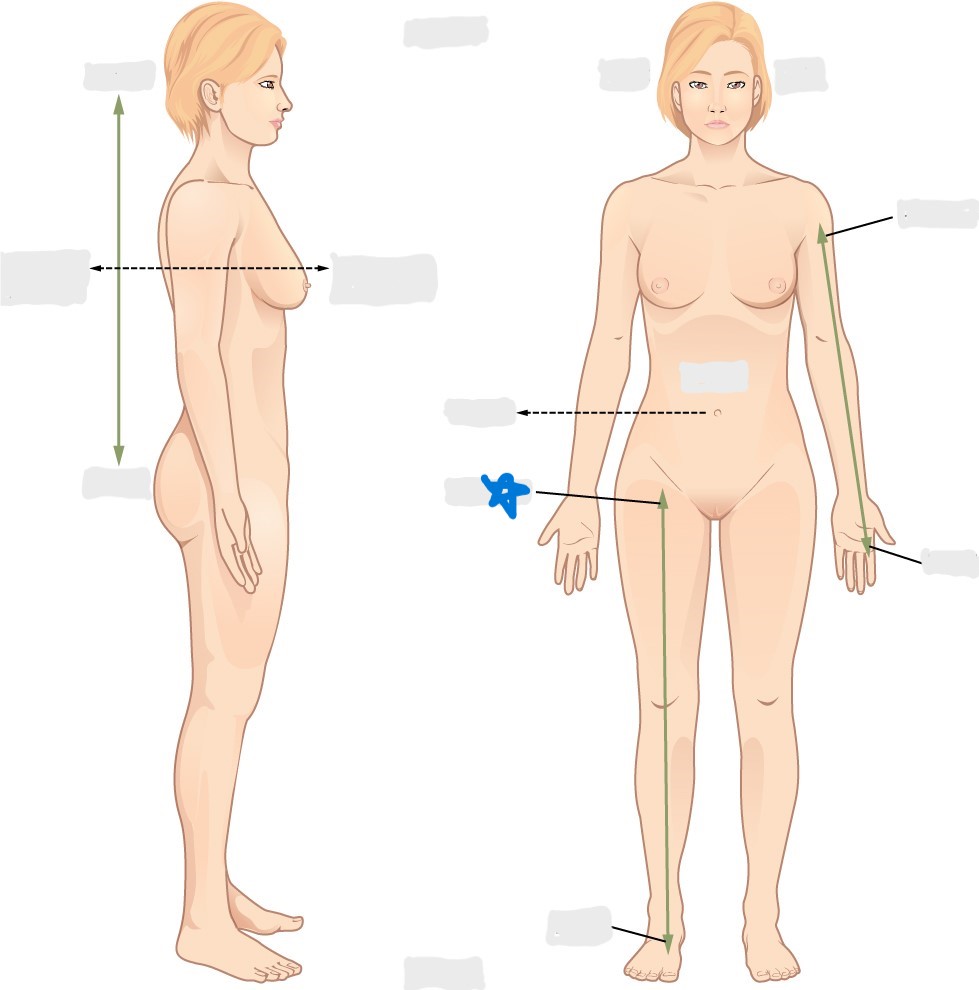

axial

appendicular

acromial

brachial

antecubital

olecranal

antebrachial

carpal

manus

coxal

femoral

patellar

popliteal

crural

sural

peroneal

calcaneal

plantar

sagittal plane

frontal/coronal plane

transverse plane

dorsal/posterior

ventral/anterior

lateral

medial

distal

proximal

superficial

deep

superior

inferior